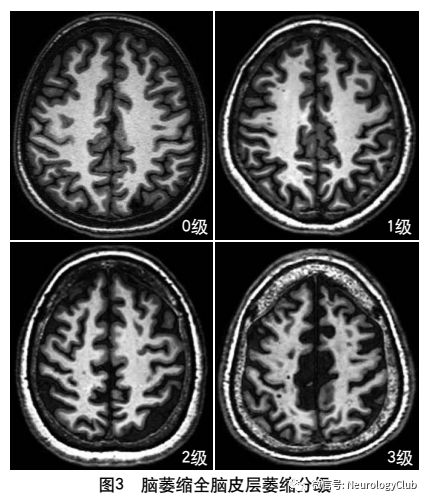

4.2.6 脑萎缩

2013年的共识指南将脑萎缩定义为与特定的局灶性损伤,如脑外伤或脑梗死无关的脑容积减少脑萎缩可以是广泛的或局部的(如特定的脑叶或海马等特定区域),可以是对称或不对称的,亦可以是组织选择性的(如发生在白质等某一特定组织层)目前不同部位的脑萎缩有相应的诊断标准,全脑皮层萎缩分级用于评价全脑(图3);内侧颞叶萎缩分级主要评价颞叶内侧,重点是海马(图4);Koedam分级主要评价顶叶,尤其是扣带回和楔前叶(图5);Kipps/Davies分级主要评价额颞叶(图6)推测脑组织减少是由脑沟(周围)和脑室(中心)的脑脊液空间相对于颅内容积扩大所引起的